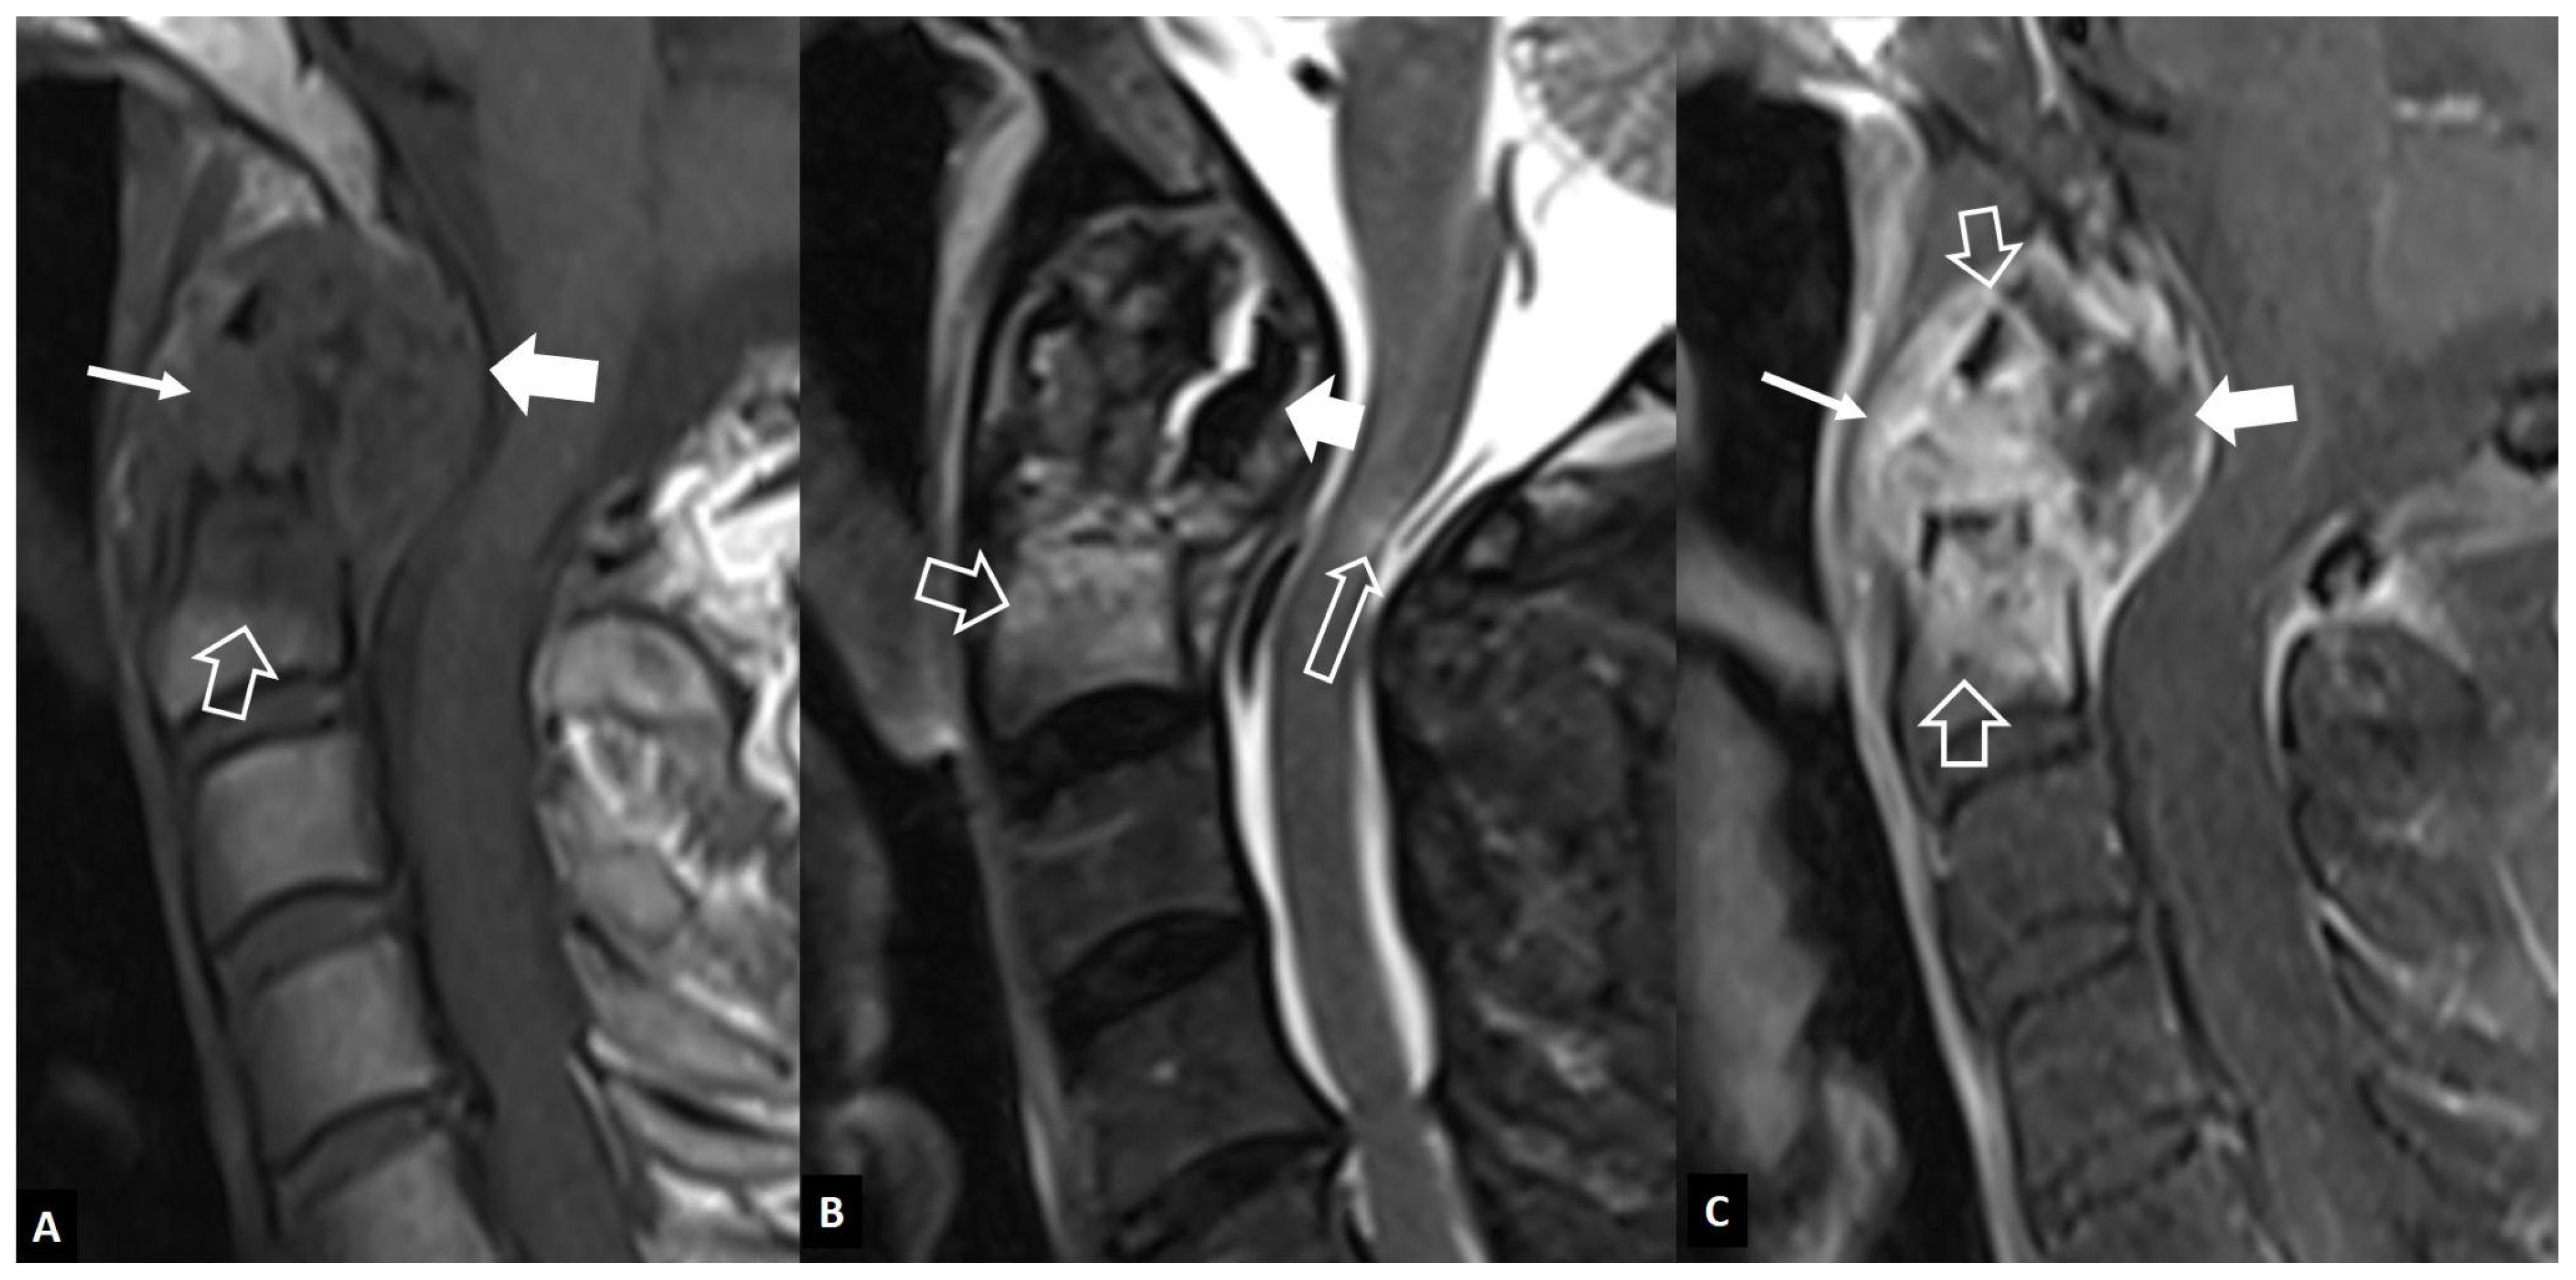

2.2. Non-Infectious Sacroiliitis

3. Long Bones